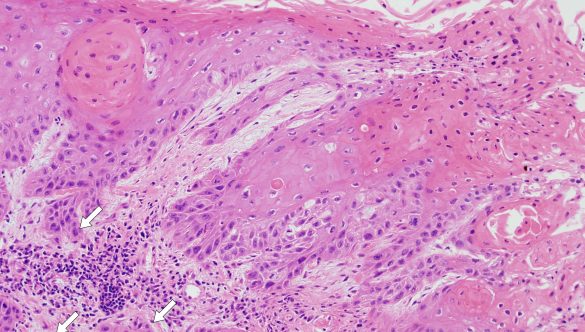

Chirurgie orala